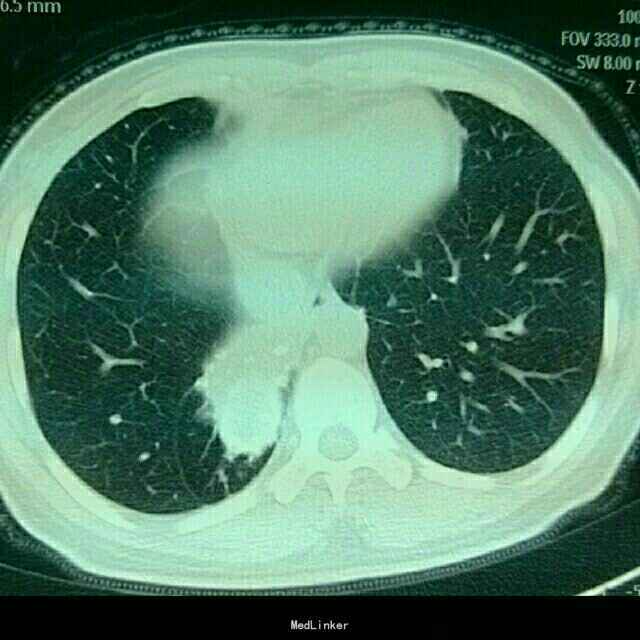

陈旧性肺结核ct图片

陈旧性肺结核ct图片,肺结核的ct图片

是否陈旧性肺结核

右肺下叶陈旧性肺结核致毁损一例.

陈旧性肺结核

相关病变:陈旧性肺结核,纤维空洞型肺结核(双上肺多见,呈条索状);间